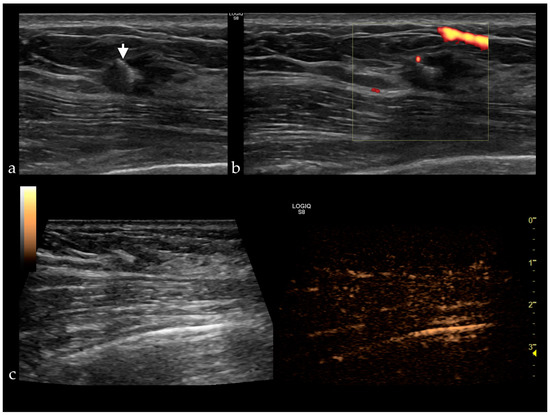

Figure 2. (a) Gray-scale ultrasound reveals a HER2 positive breast cancer presenting as a hypoechoic, non-circumscribed lesion with a clip placed in the center (white arrow), without vascularization (b) and no enhancement after contrast administration (c).

Her2 is a protooncogene on chromosome 17q. Its overexpression is associated with a lesion’s malignant transformation, rapid progression and occurrence of metastases and a poor prognosis. Tumors with positive Her2 present high enhancement and perfusion defects (Figure 2) [9,17,26,29,30].